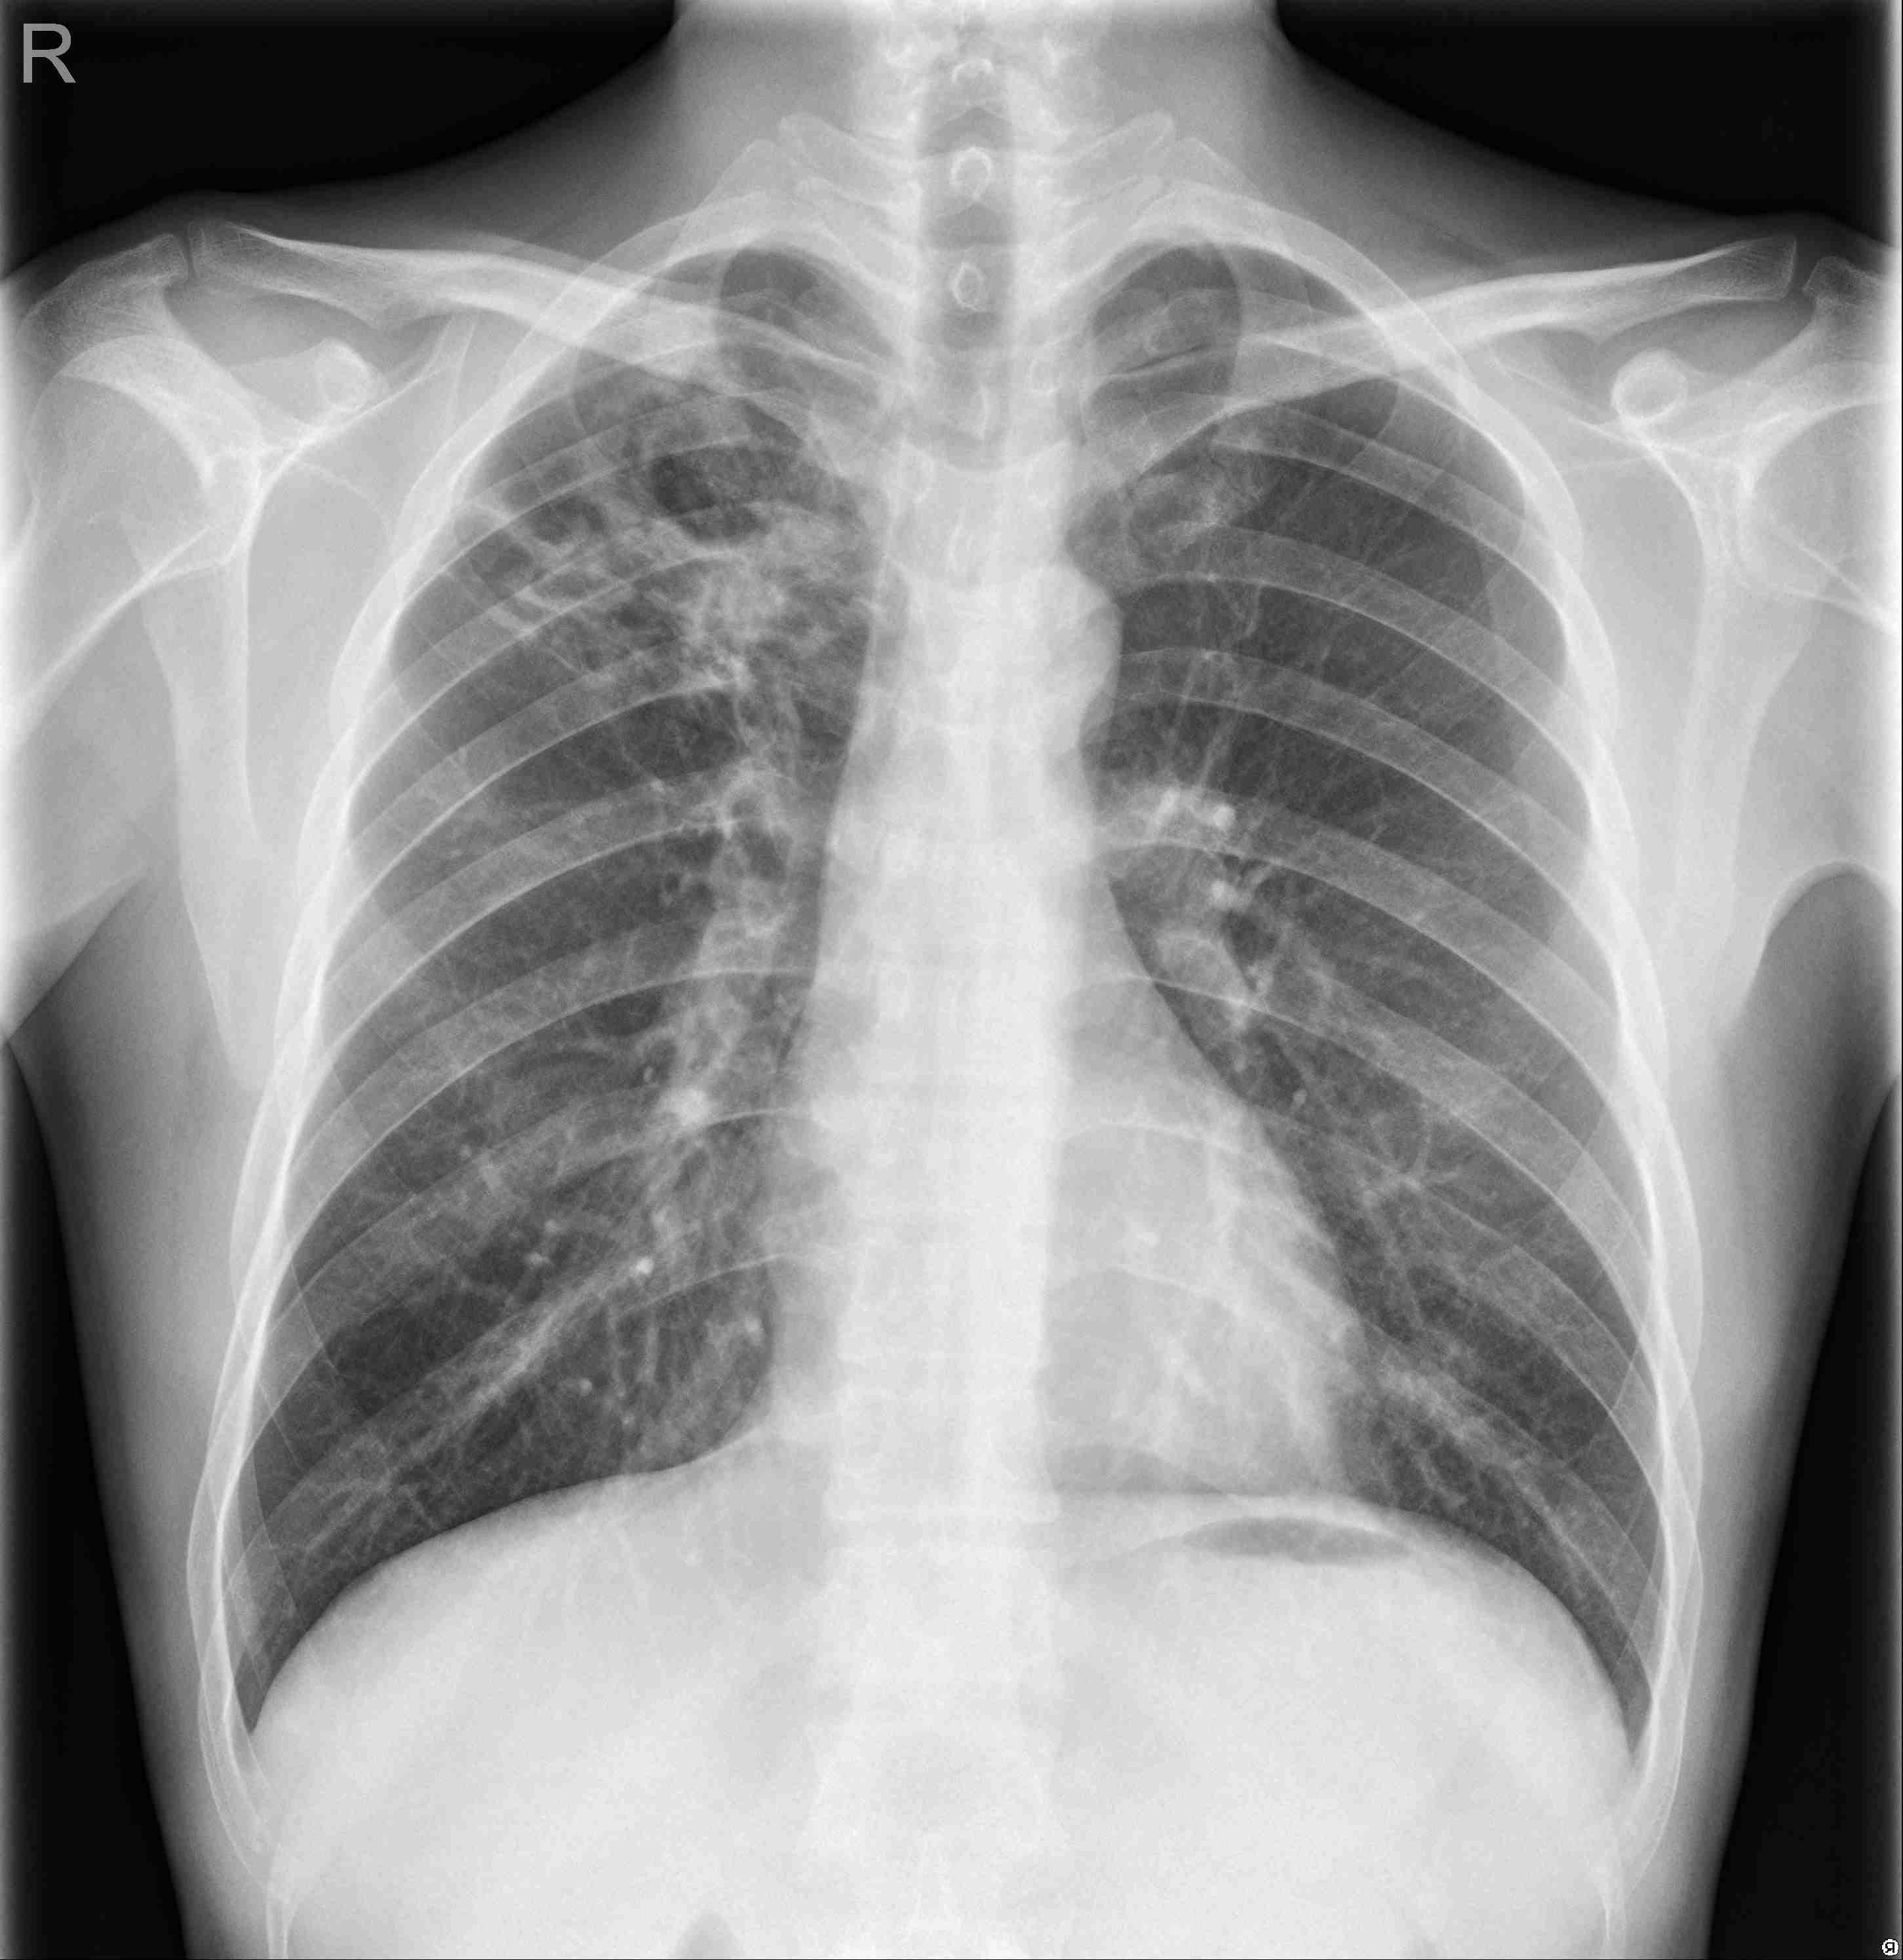

Pneumonia Analyzer

Results

Predict